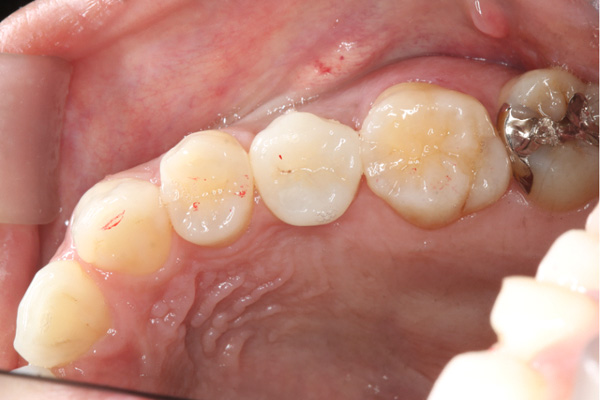

| 年代・性別 | 50代 男性 |

|---|---|

| 主訴 | 右下の歯が割れてしまったのでインプラントをして欲しい |

| 治療期間 | 約6ヶ月 |

| 費用 | 1,100,000円 |

| 治療内容 | インプラント、骨造成、結合組織移植、セラミック修復 |

| 治療に伴うリスク | インプラント周囲炎 セラミックの破折、脱離 |